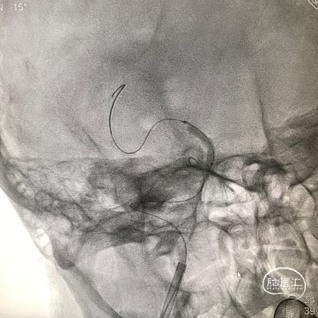

支架通过病变

支架释放

影像结论:右侧颈内动脉床突段狭窄完全解除。